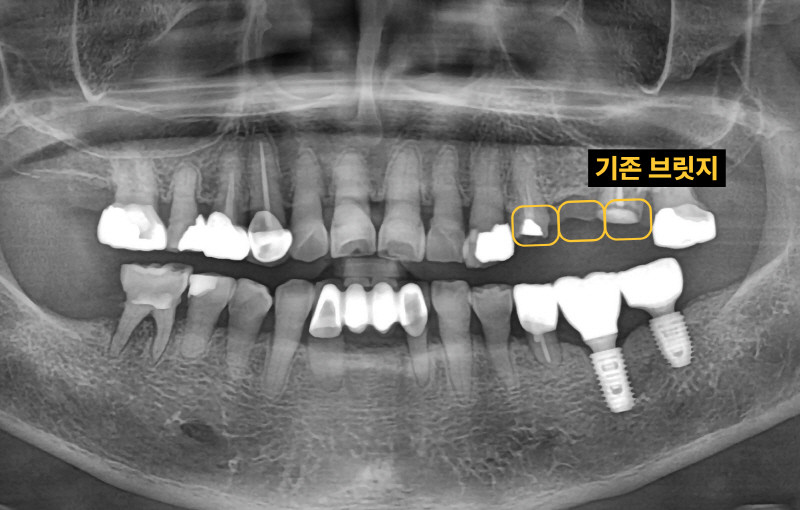

"기존 브릿지가 흔들리고 깨졌어요" 60대 여자 환자분이었습니다. 기존 브릿지를 다시 살릴 수 있는지 확인합니다.

이미 신경치료된 치아 뿌리 끝에 염증이 잡혀있고 브릿지 아래로 2차충치가 크게 생겨서 임플란트로 치료 계획을 정했습니다. 임플란트 2개를 심고 치아 머리(크라운) 3개를 만듭니다. 여러 개의 임플란트를 심을 때 꼭 개수대로 임플란트를 심을 필요는 없습니다. 과거에는 발치, 상악동 수술, 임플란트를 전부 기다리며 나눠서 진행했는데 시간이 너무 오래 걸립니다. 저는 최대한 치아가 없는 기간을 단축시키기 위해서 치아를 뽑고(발치) 동시에 임플란트를 심으며 뼈가 없는 경우 상악동 수술을 동시에 진행합니다.